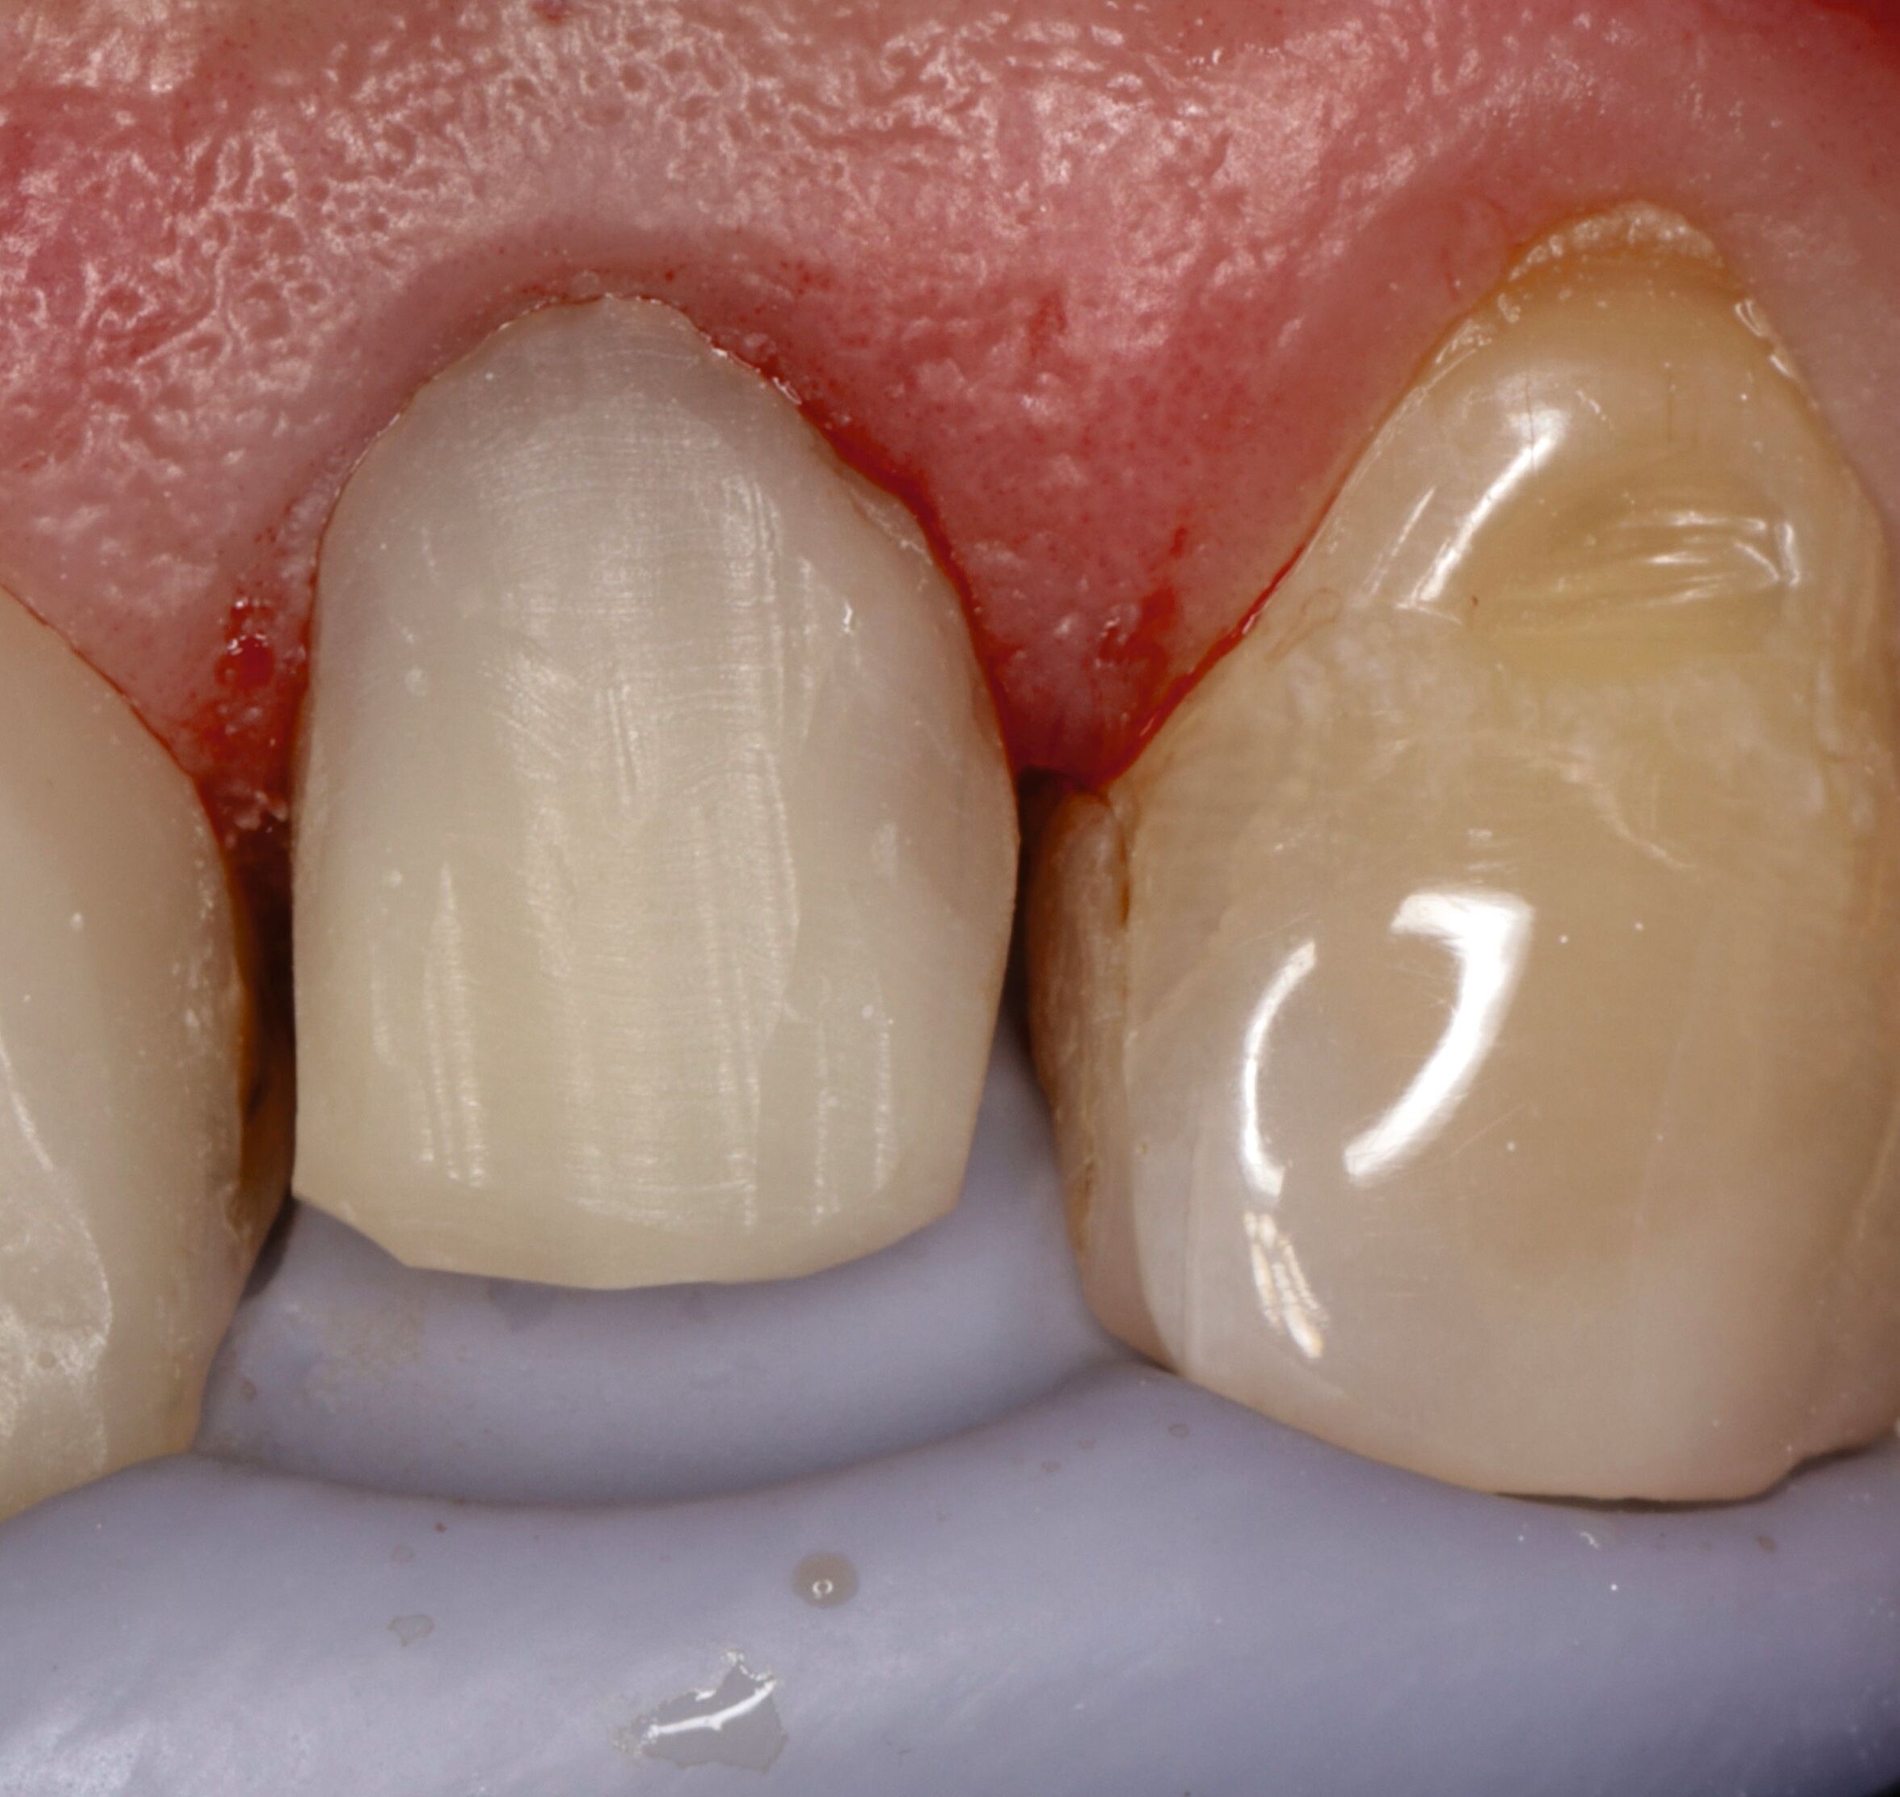

Für die restaurative Therapie von Zahn 22 wurde die alte Stiftkrone entfernt und die Stiftbohrung an die neue Indikation angepasst (Abbildungen 5a und 5b). Die Zahnkrone wurde dabei in drei Phasen wiederhergestellt: adhäsives Zementieren eines konfektionierten Glasfaserstifts, Stumpfaufbau und Modellation einer direkten Kompositkrone mit Silikonschlüssel, Frontzahnmatrize für komplexe Situationen und Schneepflugtechnik (Abbildungen 5c bis 5e) [Urkande et al., 2023; Amaro et al., 2021; Frese, 2020; Mannocci et al., 2002; Dimitrouli et al., 2011; Opdam et al., 2003]. Im Röntgenkontrollbild zeigt sich ein suffizienter Stiftaufbau (Abbildung 6).

Klasse-V-Restauration an Zahn 23

Der klassische Erosionsdefekt mit einem schmalen, zervikal gelegenen, intakten Schmelzrand sowie einer plaquefreien Oberfläche an Zahn 23 wurde mit einer direkten Kompositrestauration nach Legen eines Retraktionsfadens therapiert (Abbildung 8).